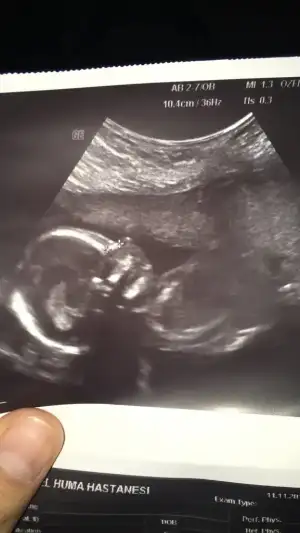

Merhaba kızlar konu başlığını bugün fark ettim 3 oğlum var 4.bebeğime hamileyim ve yarın mutlaka usg paylaşıcağım sizden yorum isteyeceğim 😊

• 78CC864D-22F1-4B60-BD75-7A7A735B23FD.webp

78CC864D-22F1-4B60-BD75-7A7A735B23FD.webp

23 KB · Görüntüleme: 53